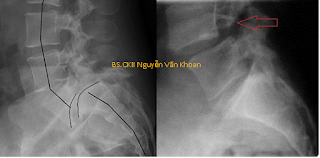

Hình X quang trên cho thấy trượt đốt sống nặng L5/S1 (hình bên trái). Trượt đốt sống L4/L5 do khuyết eo L4 (hình bên phải).